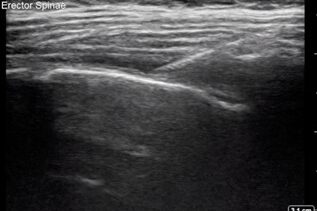

POCUS NEL CONTESTO PREOPERATORIO – CUORE Fabio Magarotto1, Federica Arturi1, Gabriele Melegari2 Università degli Studi di Modena e Reggio Emilia, Scuola di Specializzazione Anestesia e Rianimazione, Terapia Intensiva e del…